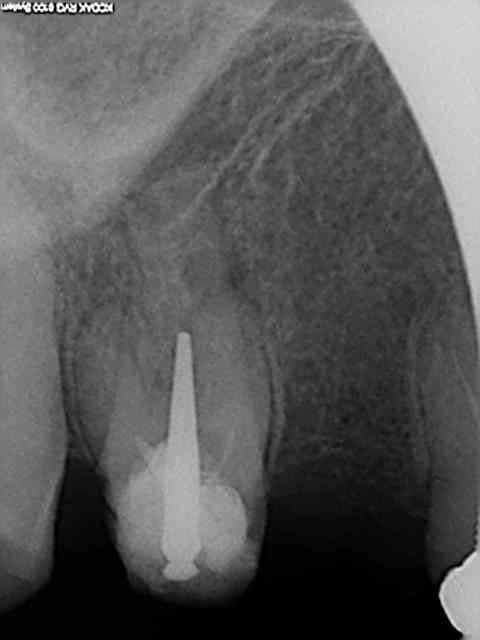

Ce genre d'omnipratique chirphil ? C'est sur c'est rentable mais one shot ! Le patient s'en souvient !

Bon après on refait un autre genre d'omnipratique mais c'est plus long (déposer le bridge l'inlay core ou le sc 33 rte ......)